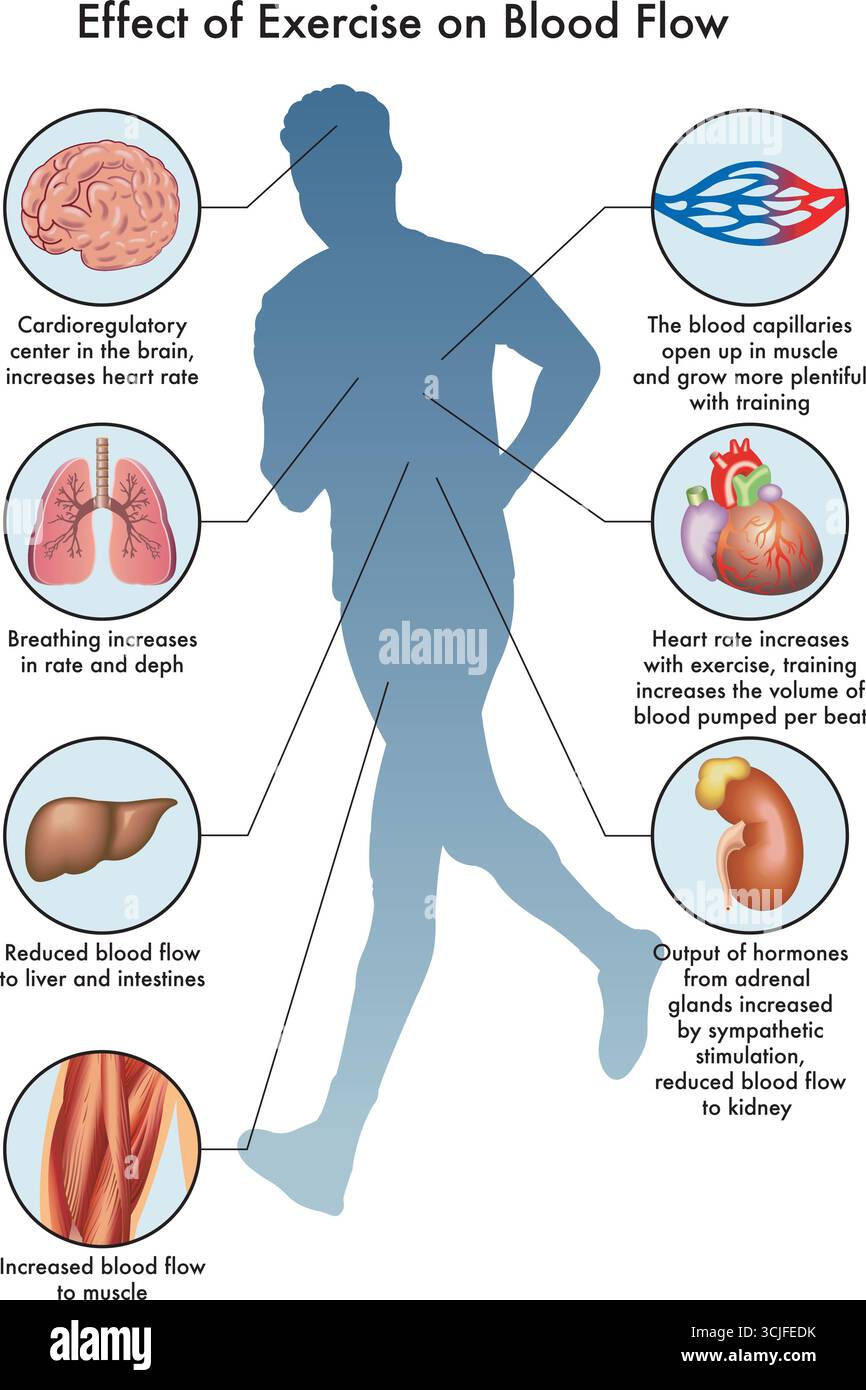

Medical illustration of Effect of Exercise on Blood Flow, with annotations. Stock Vectorhttps://www.alamy.com/image-license-details/?v=1https://www.alamy.com/medical-illustration-of-effect-of-exercise-on-blood-flow-with-annotations-image699819167.html

Medical illustration of Effect of Exercise on Blood Flow, with annotations. Stock Vectorhttps://www.alamy.com/image-license-details/?v=1https://www.alamy.com/medical-illustration-of-effect-of-exercise-on-blood-flow-with-annotations-image699819167.htmlRF3CJFEDK–Medical illustration of Effect of Exercise on Blood Flow, with annotations.